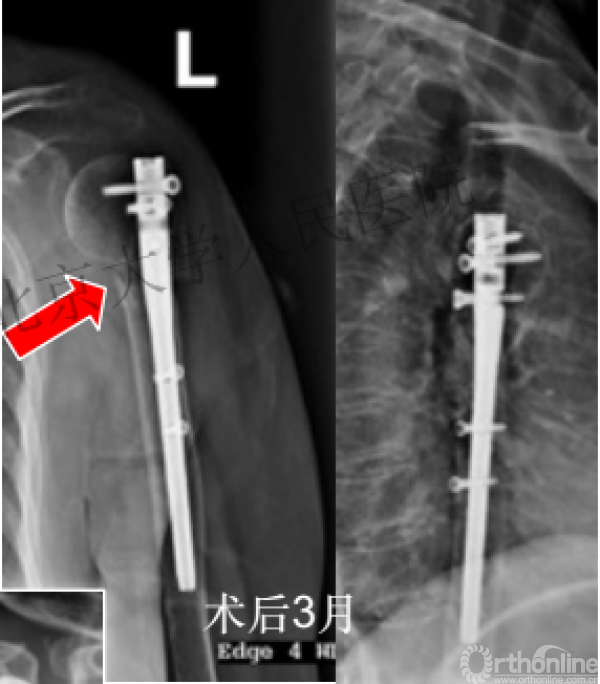

术后3月随访:继发性颈干角变小22°(5-82),肱骨头内翻,达46%

严重影响了患者的生活质量

可否有更好的进钉和复位的更好帮助办法?

进钉更完美——我们的帮助